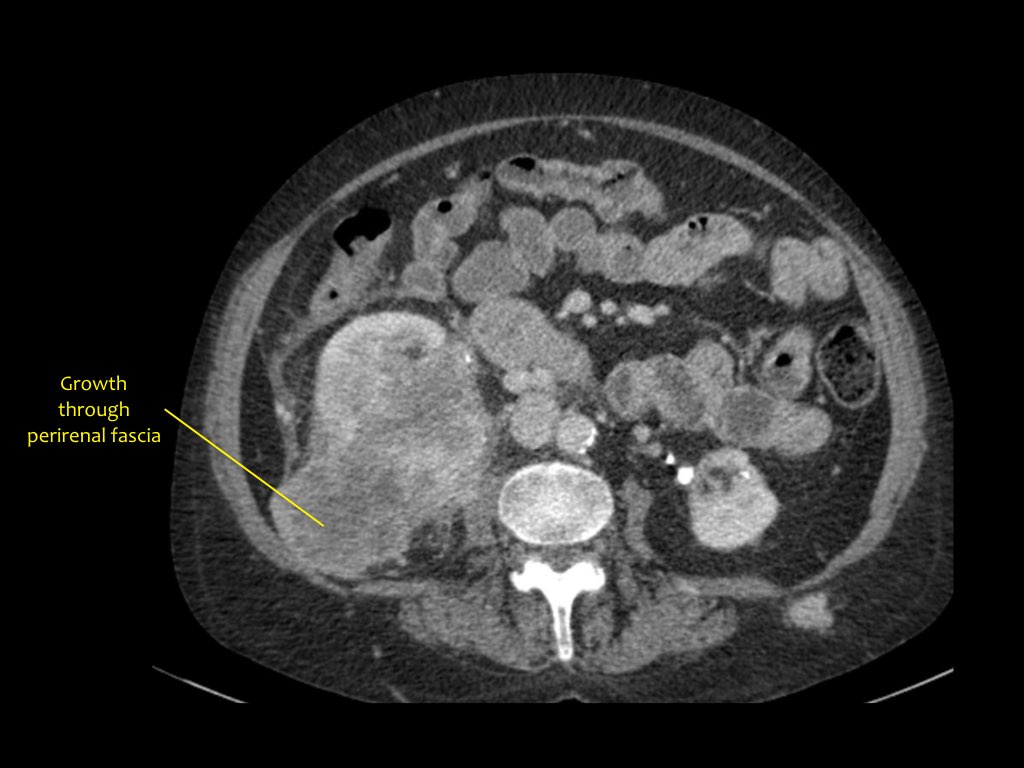

Phân giai đoạn RCC

RCC có thể xâm lấn mỡ quanh thận vượt qua cân thận và có thể lan vào tĩnh mạch thận, tĩnh mạch chủ dưới (IVC) hoặc tuyến thượng thận cùng bên.

Đối với phẫu thuật viên, điều quan trọng là cần biết có huyết khối u trong IVC hay không và liệu huyết khối có lan vào lồng ngực trên cơ hoành hay không (cần có phẫu thuật viên lồng ngực trong ca mổ).

Khoảng 25% bệnh nhân đã có di căn tại thời điểm chẩn đoán.